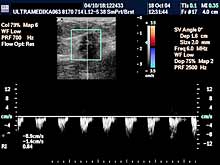

- 3D CPA - multiplanarna procena građe krvnih sudova tumora - radi

procene dobroćudnosti ili zloćudnosti opisane promene.

- Broad band-CD i CPD tehnika

- koja omogućava procenu krvnih sudova, tj. novoformiranih kapilara

koji imaju patološke vrednosti otpora i brzine proticanja krvi u

njima.

- Broad band-CD (Color-DoppIer) - pruža znatno precizniju procenu

brzine i otpora proticanja krvi u krvnim sudovima, jer je moguće

registrovati različite brzine svih eritrocita. Zbog toga je znatno

preciznija i procena protoka krvi u krvnim sudovima tumora, nego

kod konvencionalne kolor-Doppler tehnike.

- CPD-ova tehnika "broji" eritrocite i registruje intenzitet

protoka. Za razliku od konvencionalne CD tehnike omogućava

određivanje otpora (Reziostent-nih i Pulzativnih indeksa) u

najsitnijim krvnim sudovima koji se formiraju u početku rasta

tumora.